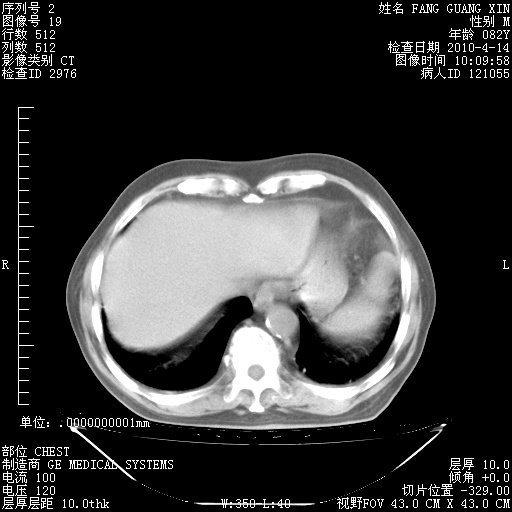

4月28日肺部CT——再次出现类似去年5月9日——透光度降低,(影像科认为)“间质性”改变。

4月28日肺部CT——再次出现类似去年5月9日——透光度降低,“间质性”改变。